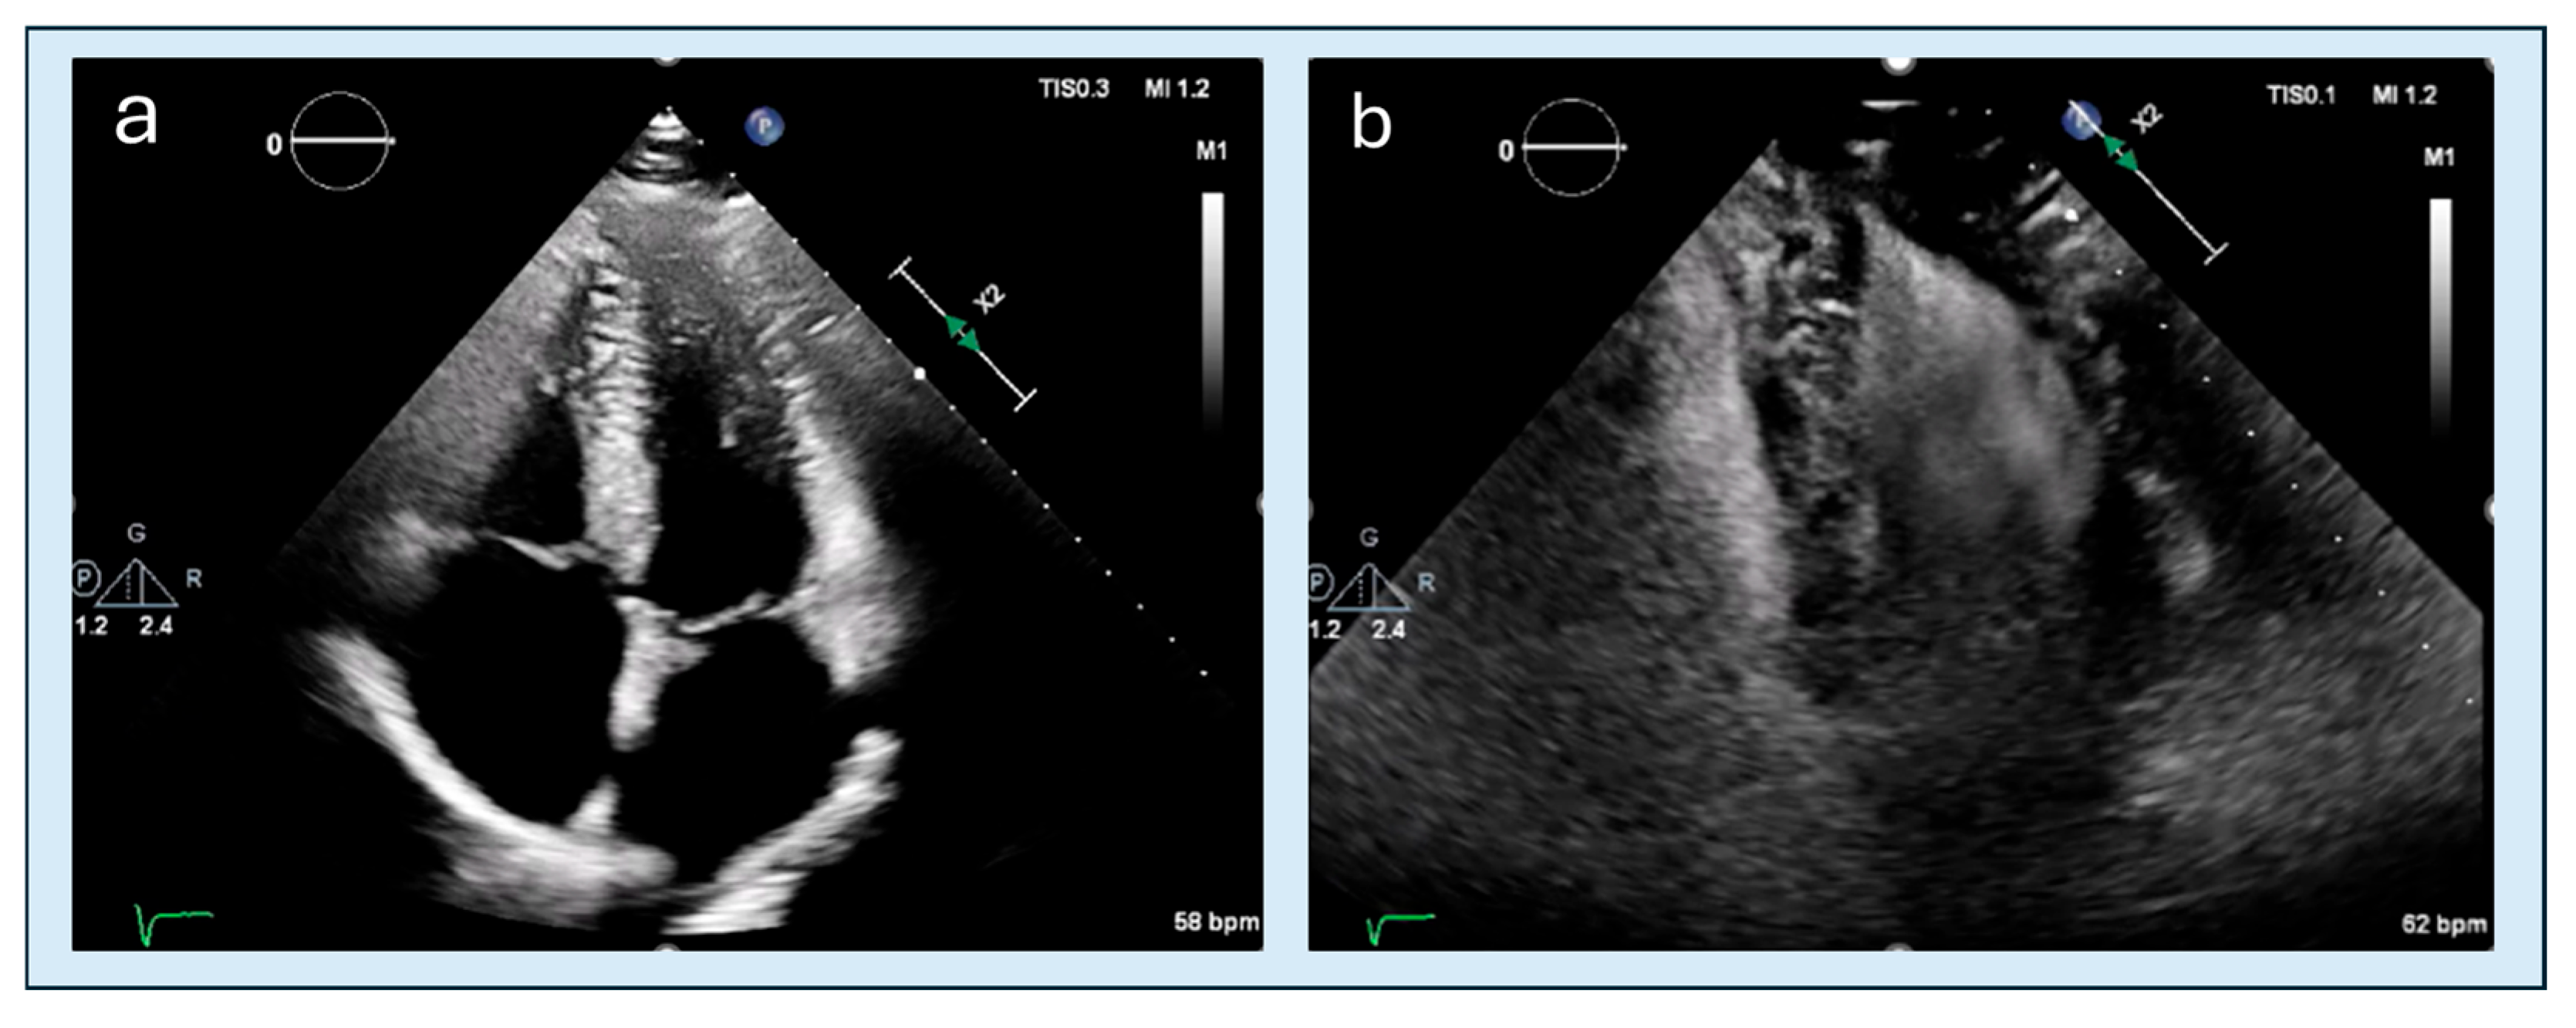

4.2. Apical Obliteration

- Po, J.R.; Kim, B.; Aslam, F.; Arabadjian, M.; Winson, G.; Cantales, D.; Kushner, J.; Kornberg, R.; Sherrid, M.V. Doppler Systolic Signal Void in Hypertrophic Cardiomyopathy: Apical Aneurysm and Severe Obstruction without Elevated Intraventricular Velocities. J. Am. Soc. Echocardiogr. 2015, 28, 1462–1473. [Google Scholar] [CrossRef]

- Sherrid, M.V.; Bernard, S.; Tripathi, N.; Patel, Y.; Modi, V.; Axel, L.; Talebi, S.; Ghoshhajra, B.B.; Sanborn, D.Y.; Saric, M.; et al. Apical Aneurysms and Mid-Left Ventricular Obstruction in Hypertrophic Cardiomyopathy. JACC Cardiovasc. Imaging 2023, 16, 591–605. [Google Scholar] [CrossRef] [PubMed]